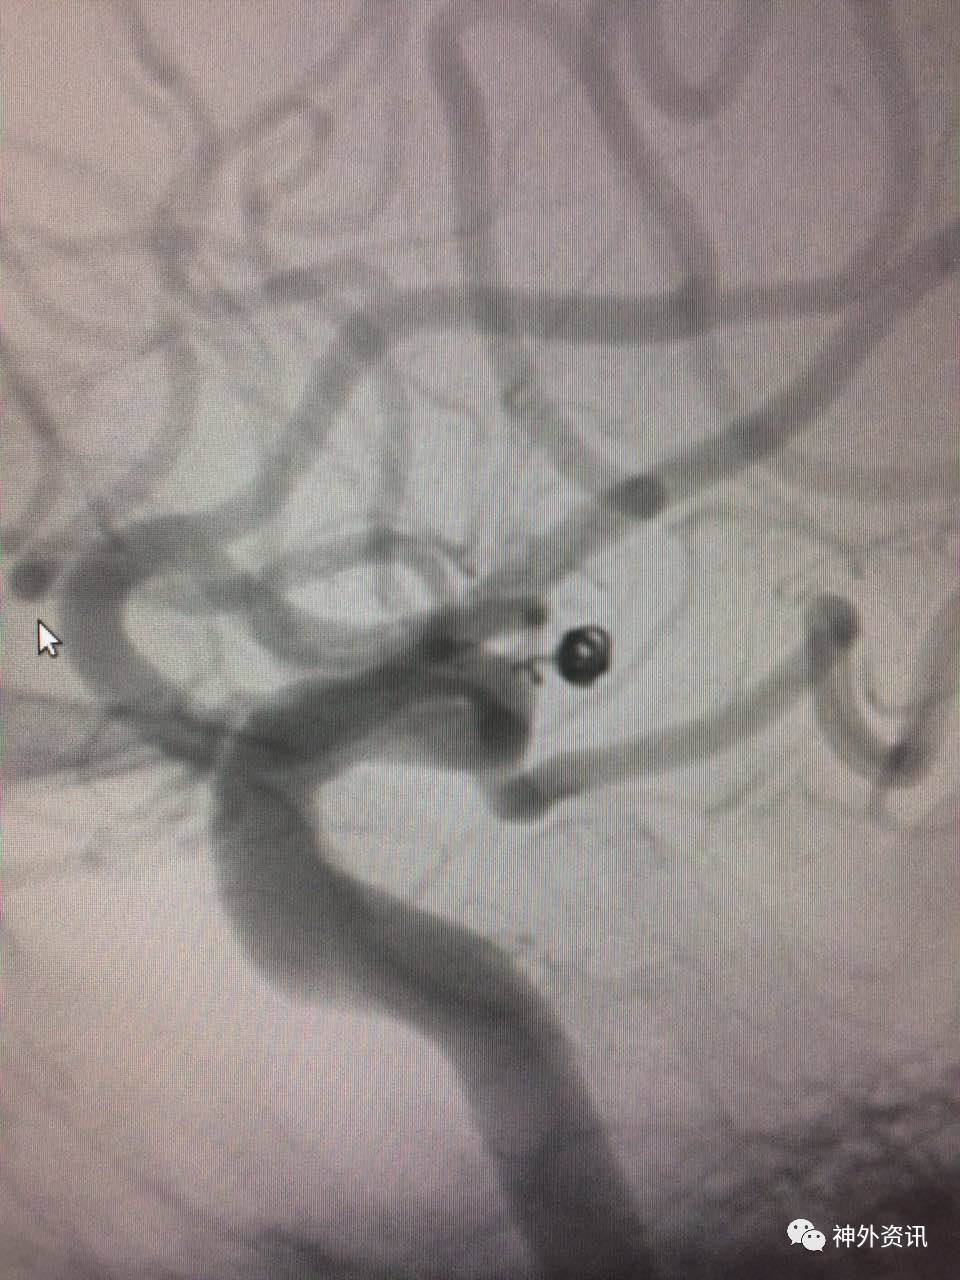

病例一

病例二

病例三

病例四

病例五

病例六

病例七